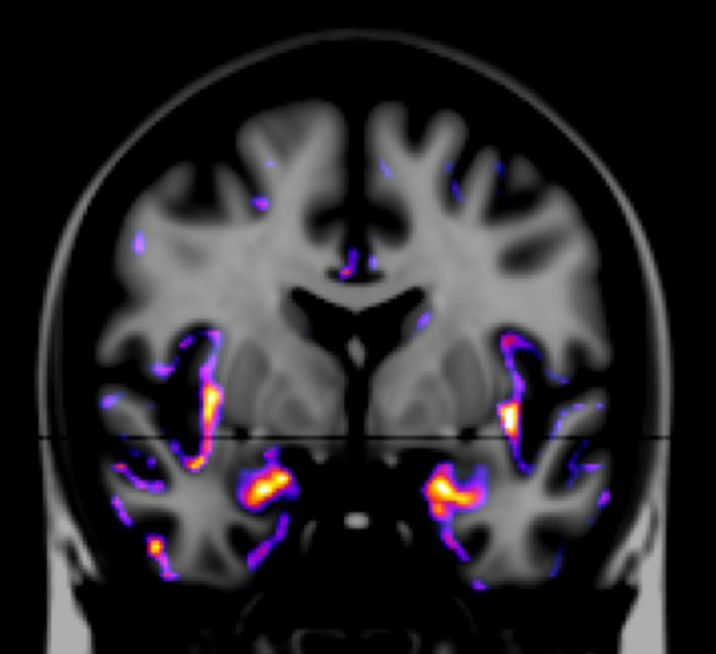

fMRI(functional MRI)​

脳の生理機能を測定する技術です。脳の神経活動によって変化する血流動態や代謝産物による信号差を画像化します。

特定のタスクを実行しているときの脳の生理機能の変化を可視化することができるので、神経科学や心理学など多くの研究に利用されています。​​

刺激によって脳のどの領域が興奮しているかを表しています。

上:ラット左後肢への疼痛電気刺激における脳の反応領域を評価

下:ラット右眼への光刺激における脳の反応領域を評価​